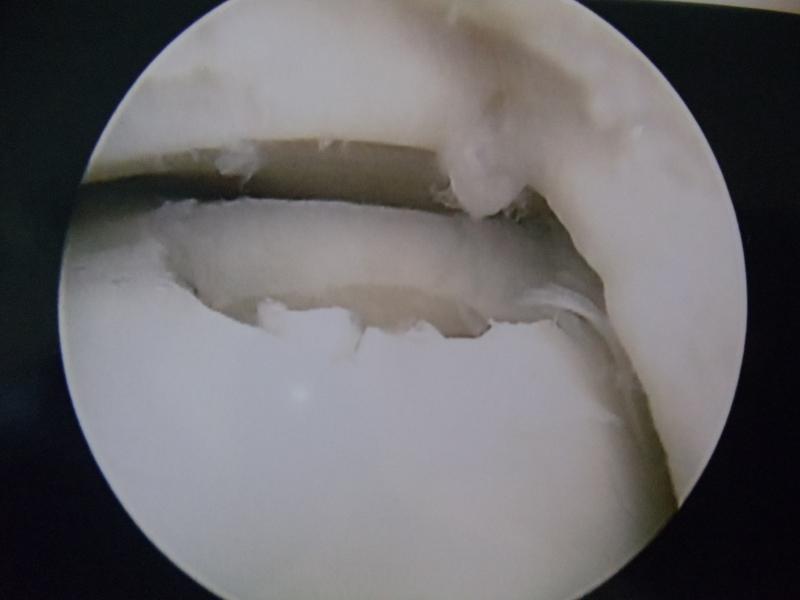

Impingement-ul (conflictul) la nivelul gleznei poate apărea anterior sau posterior, cauzând durere și limitarea mobilității articulației, până la blocaj. Impingement-ul articular anterior al gleznei este asociat leziunilor entorselor, prin osteofite și ligamente cicatrizate prinse între tibie și astragal.

Impingement-ul talar posterior al gleznei se face în timpul flexiei plantare, când osul trigonum (fragment posterior al talusului) este prins între tibie și calcaneu, împreună cu țesuturile adiacente. Conflictul limitează flexia și produce durere posterioară de gleznă.

Tratamentul artroscopic presupune debridarea articulară, respectiv înlăturarea aderențelor articulare – țesuturi, osteofite (proeminențe osoase) sau fragmente osoase.